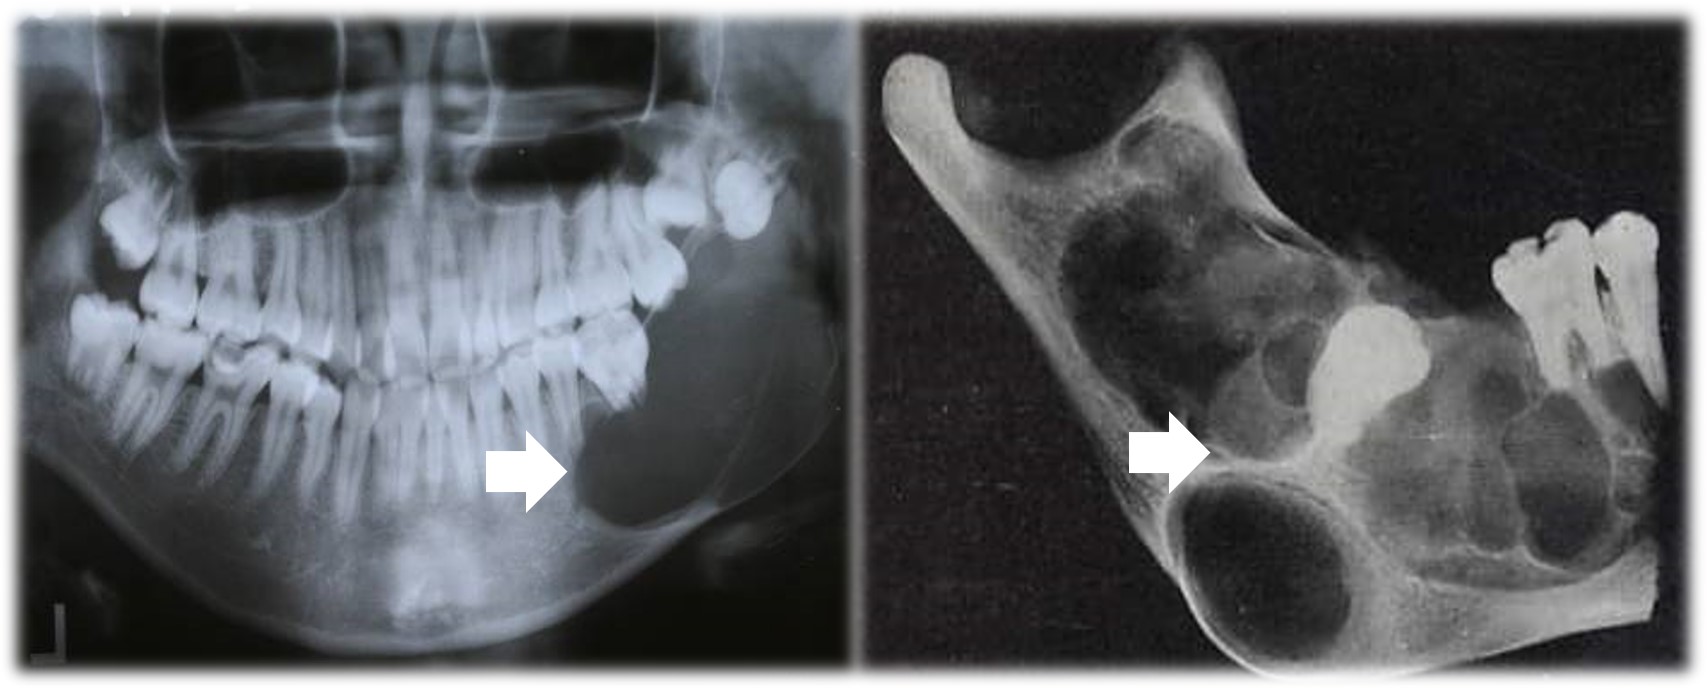

X线表现为单房或多房性透射影,边界清楚,牙移位、牙根吸收,埋伏牙类似含牙囊肿(图14.1-1)。

图14.1-1 成釉细胞瘤(X线)

X线表现为单房透射影(图14.1-10)。

图14.1-10 单囊型成釉细胞瘤(X线)